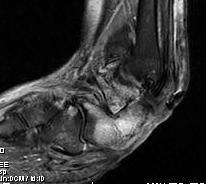

- MRI

Charcot arthropathy

Midfoot ulcer with evidence of underlying Charcot arthropathy and midfoot collapse

www.boneschool.com/charcot-foot